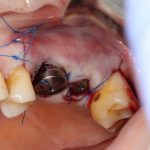

Напомню, что для этой работы я выбрал субкрестальные имплантаты Ankylos C/X. Они прекрасно сочетаются с любым методом остеопластики.

Я не планирую установку супраструктур или коронок, поэтому на уровень первичной стабильности можно положить болт. Даже наоборот — чем меньше крутящий момент при установке, тем лучше. Для имплантатов Ankylos и подобных им, это особенно важно. В общем, момент силы при установке — не более 10-15 Нсм.

Ремарка: имплантаты с предустановленными имплантодержателями хороши тем, что с ними легко контролировать позиционирование имплантатов. В случае с Ankylos С/Х - еще и крутящий момент. Имплантодержатель должен отсоединяться от имплантата с легким щелчком. Если его клинит, и тебе приходится прикладывать для этого усилия, то ты, однозначно, превысил момент силы во время установки имплантата. Следовательно, жди проблем.

Глянем на то, что получилось: